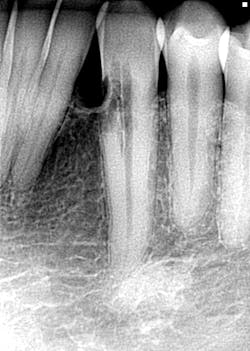

- Radiographical findings: Radiolucency on the mesial of No. 22; congenitally missing No 23 [See Figure 1.]

- Clinical findings: Occlusal pit caries No. 31; soft tooth structure No. 22 sub-g on the mesial buccal and lingual with inflammation; slight delay with cold test, WNL to percussion

- Concern: Possible external resorption on No. 22 with extent of lesion unknown; recommended assessment with an endodontist for CBT scan to assess probability of restoring; discussed very guarded nature of situation to the patient and gave the referral information needed to set up his consultation appointment